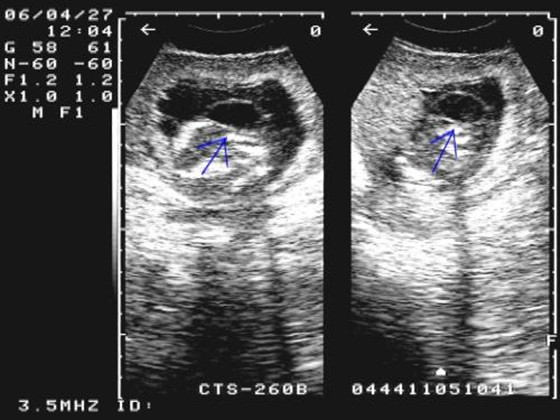

2、胚胎质量不好,即染色体的原因:如果受精卵质量不好的话,就好比土壤不够肥沃,是种不出什么优良的作物的,同理胚胎质量不好、染色体有问题,就会出现胎停的情况;